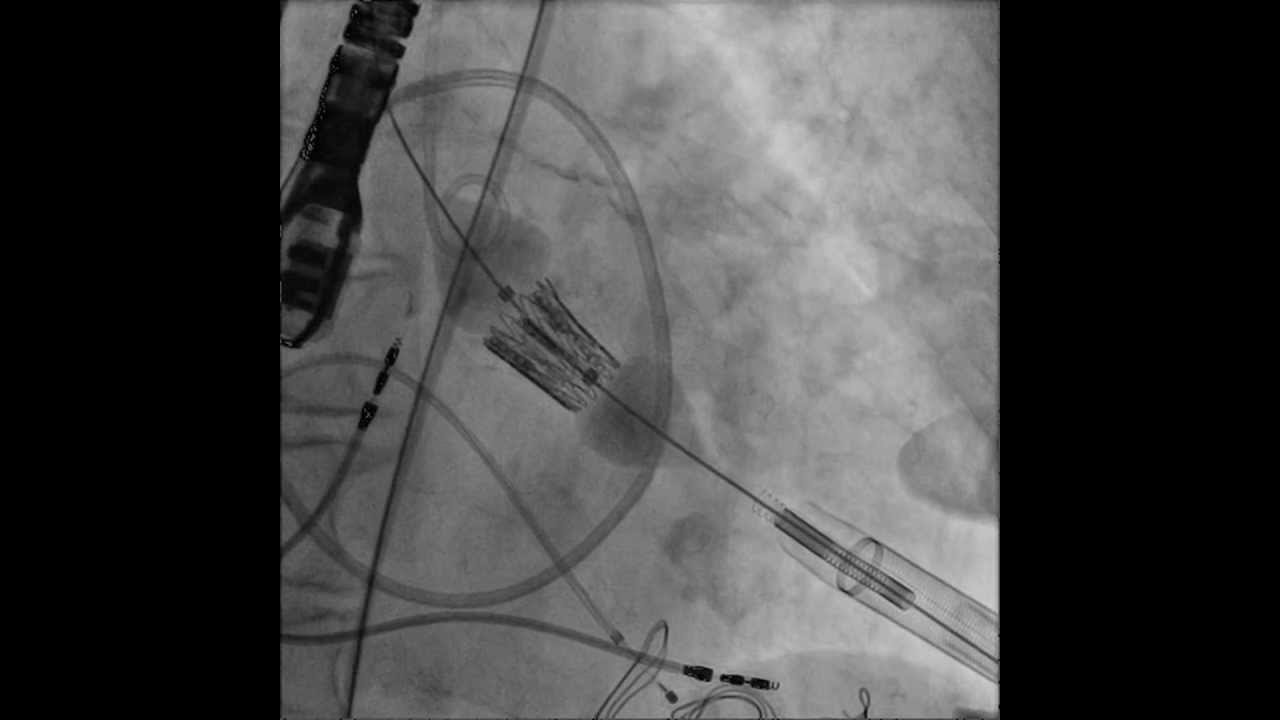

Tavr Transcatheter Aortic Valve Replacement Transapical Deployment

Transcatheter Aortic Valve Replacement Tavr Prof Dr Taylan Akgün Among 178 patients who underwent transapical transcatheter aortic valve replacement between october 2009 and july 2023, 173 patients who underwent this intervention for native aortic stenosis were included in this study, and early and long term results were evaluated. Transfemoral access is the most common approach for transcatheter aortic valve replacement (tavr). however, a subset of patients require alternative access. this study describes the evolution and outcomes of alternative access tavr at cleveland clinic. Transapical tavr allows for tavr even in the context of severe peripheral vascular disease, although it has rarely been used in the viv tavr setting, and even less frequently with concomitant percutaneous coronary intervention. The aim of the present study was to study our experience with ta tavr and explore new possibilities for alternate access sites and concomitant transcatheter repair.

Tavr Transcatheter Aortic Valve Replacement Tavr Specialist In Transapical tavr allows for tavr even in the context of severe peripheral vascular disease, although it has rarely been used in the viv tavr setting, and even less frequently with concomitant percutaneous coronary intervention. The aim of the present study was to study our experience with ta tavr and explore new possibilities for alternate access sites and concomitant transcatheter repair. Additionally, this document highlights the advancements in device technology and imaging guidance that have contributed to improving the safety and efficacy of alternative access tavr. Learn about the transfemoral and transapical approaches and techniques for transcather aortic valve replacement (tavr) patients with dr. mathew williams. Transapical transcatheter aortic valve implantation (ta tavi), a minimally invasive, beating heart surgical treatment for severe aortic stenosis, is an alternative for the traditional avr technique. Transcatheter aortic valve replacement (tavr) has become the first‐line therapy for symptomatic severe aortic stenosis. 1, 2 with the expansion of tavr indications, especially the inclusion of younger patients with longer life expectancies, the long‐term durability and performance of the valves have become increasingly important.